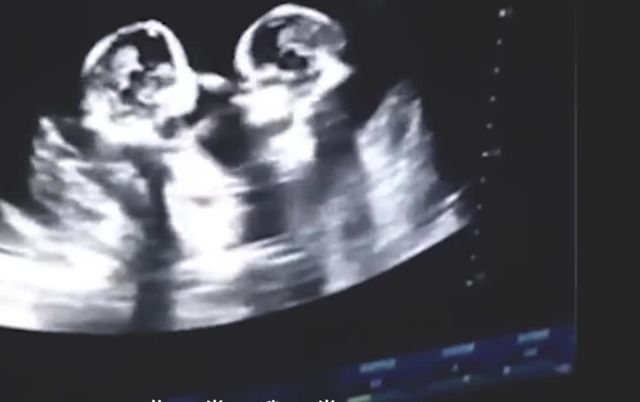

于是宝妈就来到了医院检查,也就发现了这样一幕,在医生的B超下显示,这两位双胞胎非常的不安分,它们竟然在宝妈的肚子中打起了架,是你踢我一脚,我打你一拳的,让人感到非常的滑稽。

这虽然给宝妈带来了困扰,不过宝妈在看完之后,也是感到非常的幸福,不少网友也表示:这哥俩还真挺好,从小就相依相偎的,对此,小伙伴们是如何看待的?